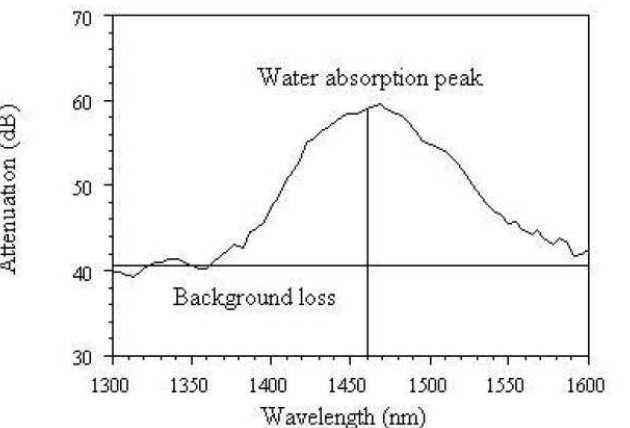

Radio frequency (RF) tissue fusion is a novel method of tissue approximation that can seal tissue without the need for sutures or staples, based on tissue transformations induced by Joule heating and mechanical pressure. RF delivery must be controlled and optimised to obtain a reproducible, reliable seal. At present, tissue impedance is used for feedback during RF blood vessel sealing. We have developed a method of real-time optical measurement to improve understanding of the tissue modifications induced by RF fusion. Near infrared transmission spectroscopy has been used for dynamic acquisition of the tissue attenuation spectrum, and the modified Beer-Lambert law has been used to extract optical parameters. Simultaneous temperature measurement shows that tissue coagulation alters scattering losses and that tissue dehydration induces changes in the water absorption band near 1450 nm wavelength.

|

|---|

| Water absorption band in pig bowel tissue |